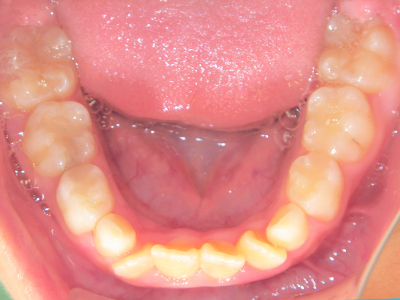

小児矯正について

歯並びの相談に来られるお子様は、口呼吸をしているケースが多く、これが歯並びに大きな影響を与えています。

ないき歯科クリニックでは、上あごの成長不足を補い、鼻呼吸を獲得しつつ歯列を整え、将来のお口をより健康な状態にすることをゴールに定める矯正治療をおこなっています。